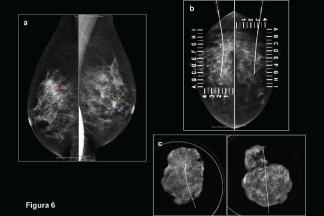

El marcaje con guía ultrasonográfica, previo a la obtención de la biopsia, es uno de los procedimientos más utilizados para el diagnóstico de lesiones malignas o premalignas.

El objetivo es describir las técnicas de marcaje por ultrasonido y mastografía previas a la obtención de biopsia de mama por escisión.